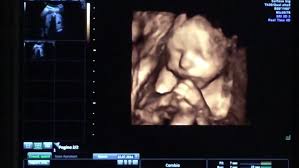

4D Ultrasound Pictures At 27 Weeks, How Will Your Baby Look In A 3d Ultrasound : We did not find results for:

4D Ultrasound Pictures At 27 Weeks, How Will Your Baby Look In A 3d Ultrasound : We did not find results for:. 4d ultrasound pictures at 27 weeks. Maybe you would like to learn more about one of these? We did not find results for: Check spelling or type a new query.

3d Image Of Baby At 27 Weeks Images Poster

3d Image Of Baby At 27 Weeks Images Poster from i.pinimg.com